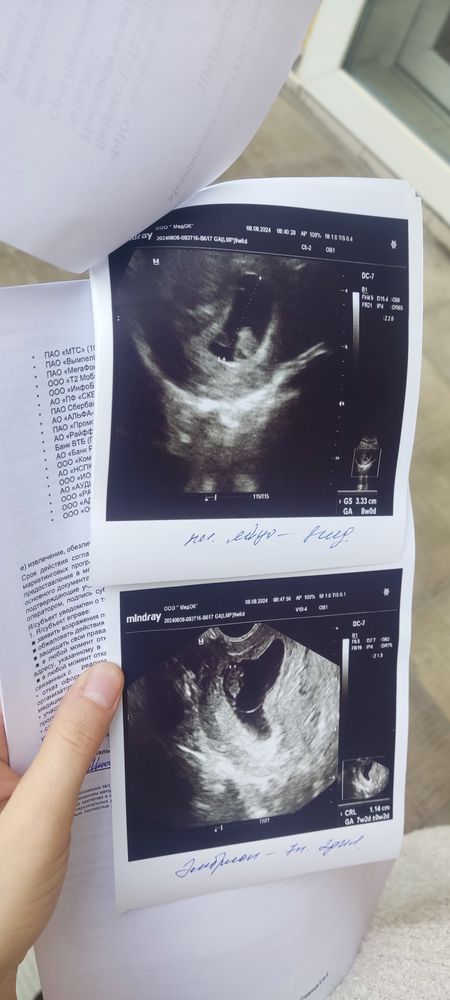

Подскажите про УЗИ

Все норм в узи, тонус отдыхать больше ❤️

Нормальное УЗИ ,тонус бывает у многих на таком сроке.Побольше отдыхайте и не поднимайте тяжести.

Вообще у вас тонус, я бы к врачу сходила, тонус на маленьком сроке опасен